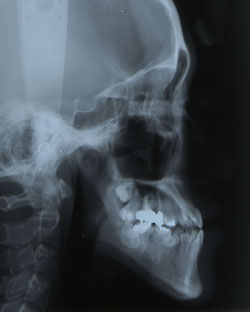

그림 2. 안면비대칭을 주소로 내원한 23세 남자환자로서 골격성 3급 부정교합과 함께 좌측의 반대교합을 보여주고 있다. menton이 심하게 좌측으로 편위되어 있어 우측과두가 좌측에 비해 과성장한 것에 의해 나타난 RM type의 안면비대칭으로 보여졌다.

그림 3. 정모두부방사선사진의 투사도를 작성하고 분석을 시행한 결과 Me은 편위된 반면 ramus length의 좌우차이는 보이지 않아 기계적으로는 M type으로 판정되었다. 그렇다면 본 환자의 이부편위는 어떻게 나타났는가?어느 부위의 좌우차이가 본 환자의 이부편위에 기여하였는지 2차원적인 방사선사진만으로 잘 파악이 되지 않는다.